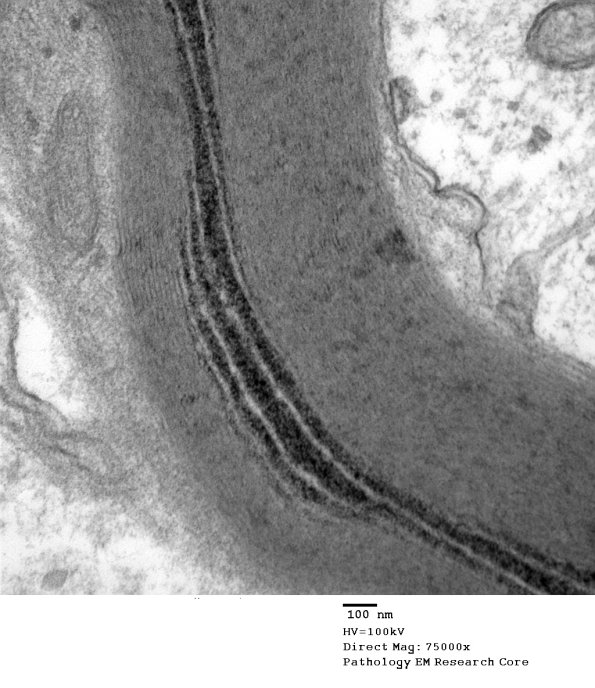

Washington University Experience | PERIPHERAL NEUROPATHY | 3 NORMAL MYELIN & SCHWANN CELLS | 3 Schmidt-Lanterman Clefts | 10B3 S-LC (Case 10) EM 157 - Copy

Higher magnification of image #10B1. (electron micrograph)